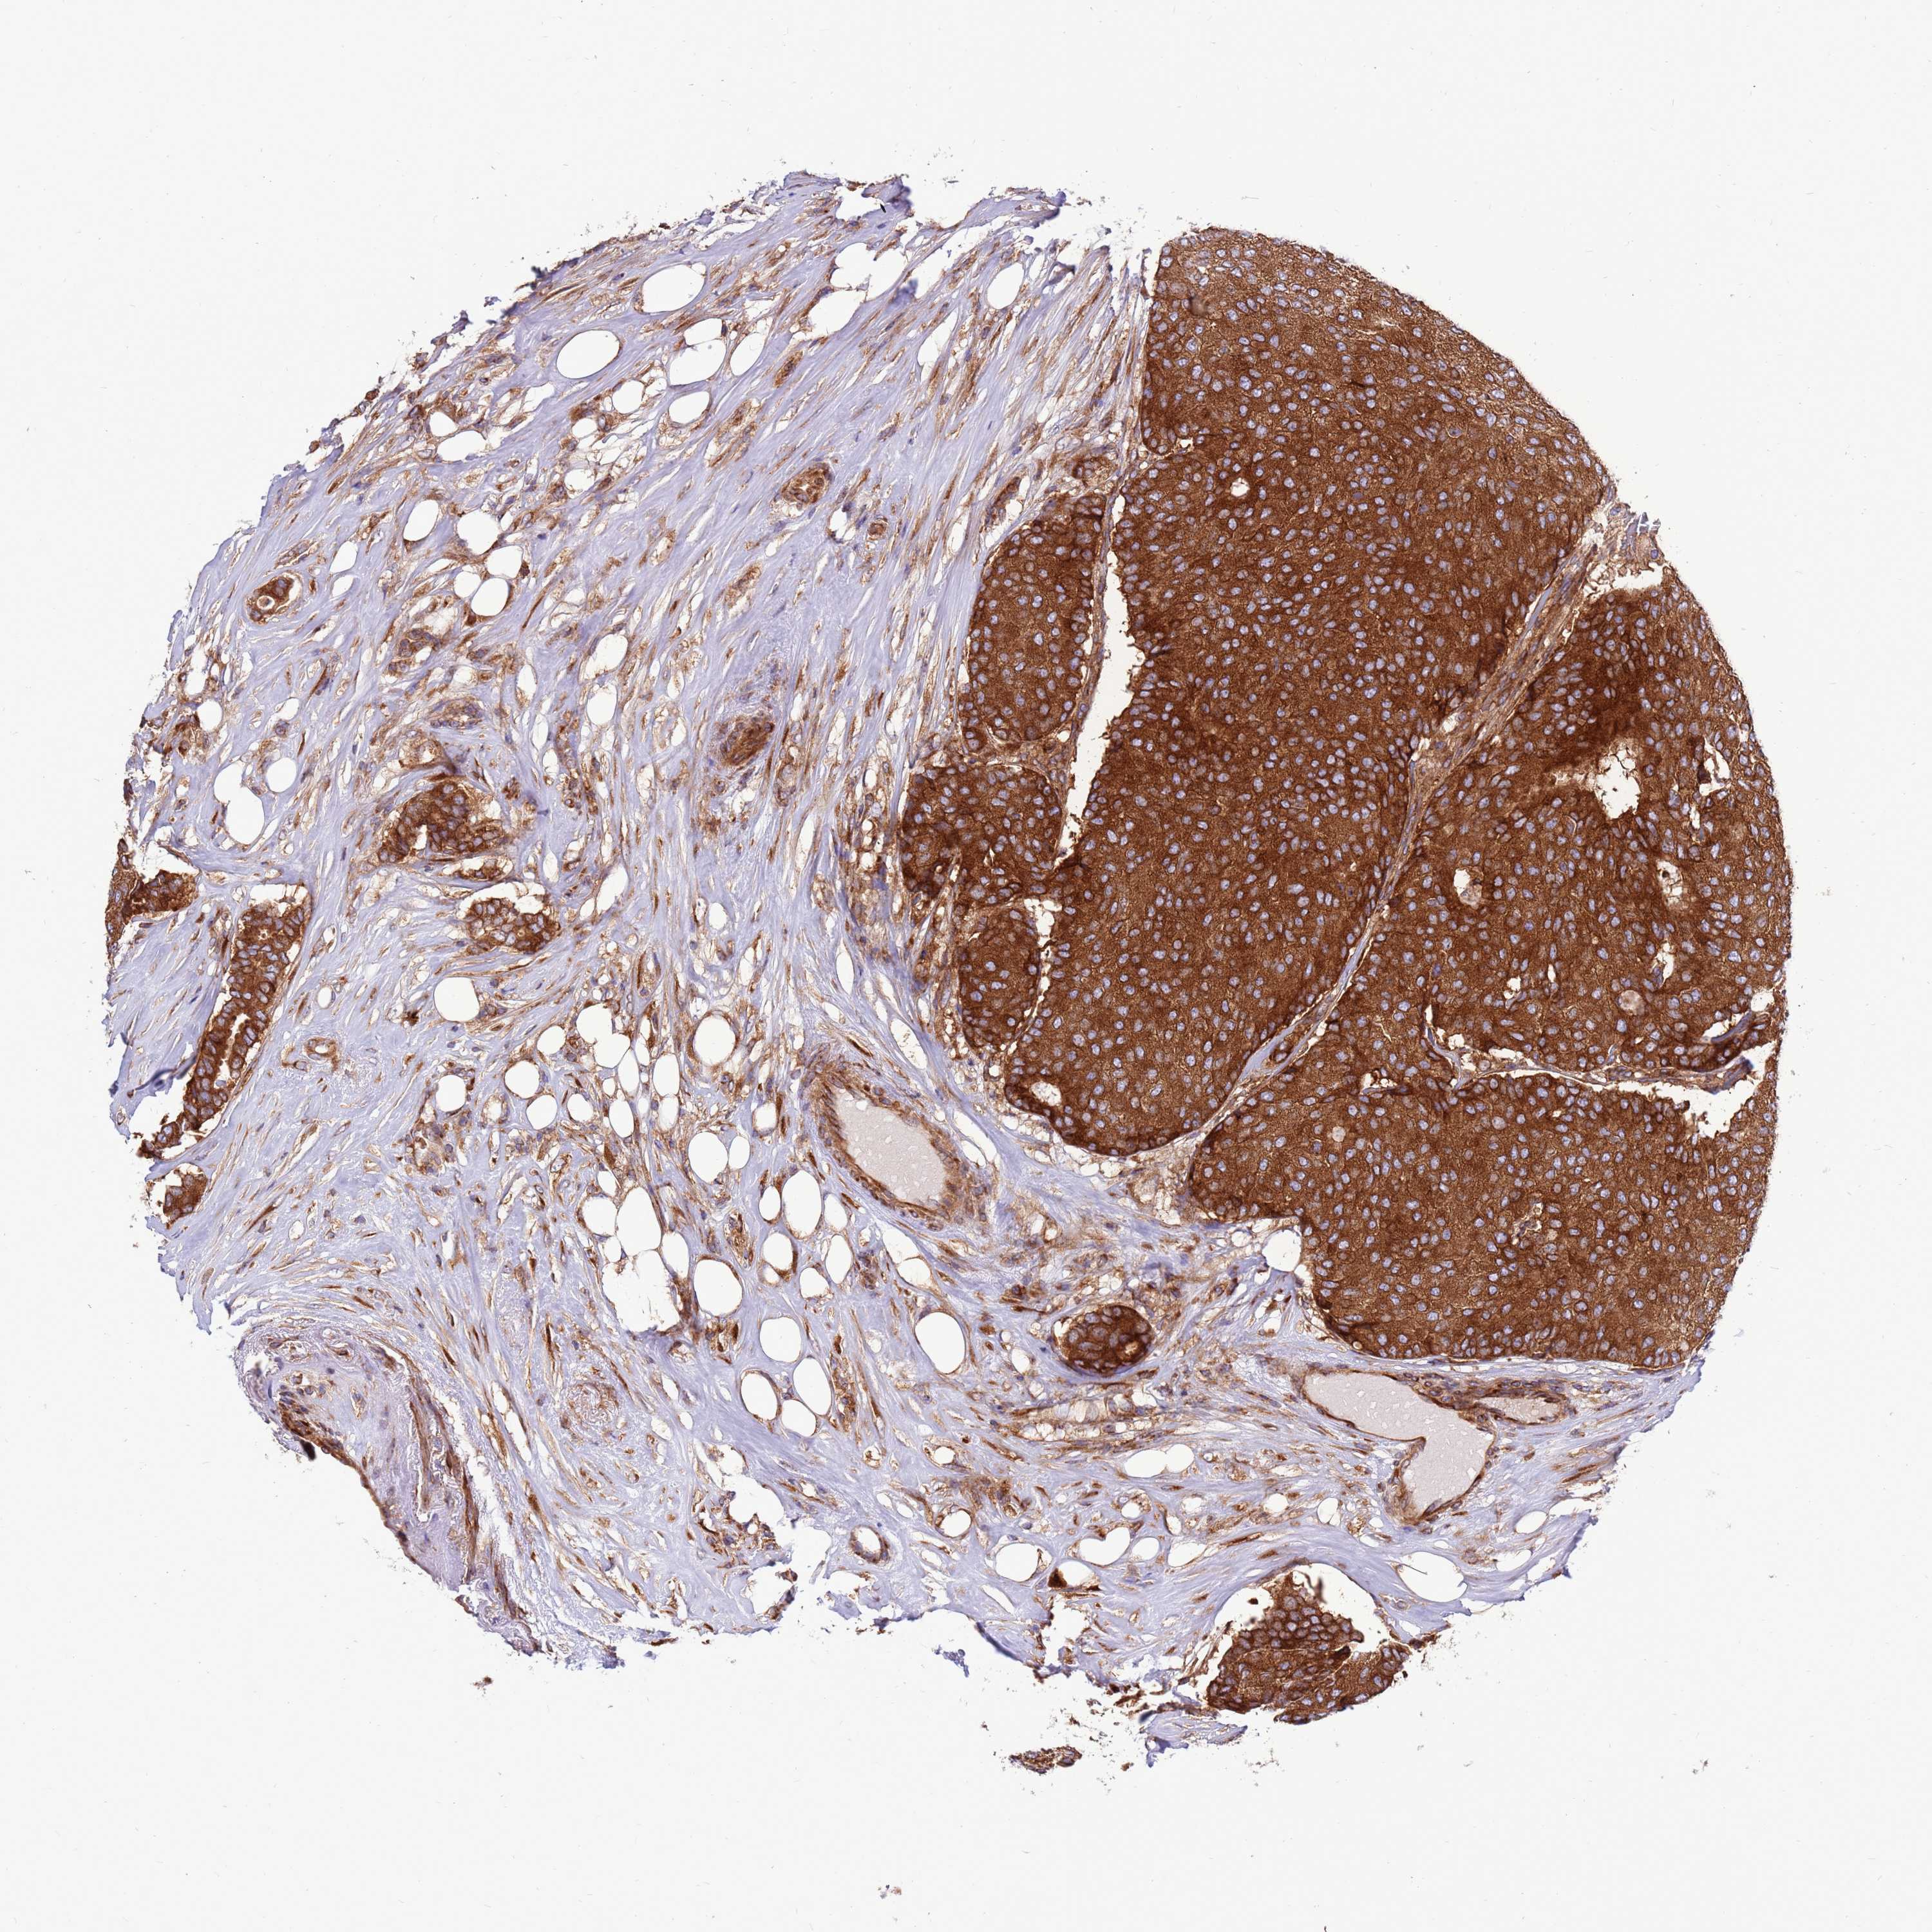

CANCER BREAST CANCER Show tissue menu

BRCA TCGA BRCA VALIDATION PROTEIN EXPRESSION